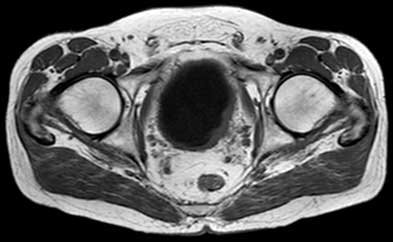

Hình 1. Hình ảnh MRI xung T1 cho thấy khối u bàng quang bên trái có tín hiệu trung gian so với tín hiệu thấp của nước tiểu trong bàng quang. Có lớp mỡ liền kề với khối u, phù hợp với giai đoạn bệnh T3b sớm.

Các chuỗi xung T1 rất hữu ích để xác định khối u nguyên phát, vì nó có thể được nhìn thấy dựa trên nước tiểu sẫm màu trong bàng quang (Hình 1). Câc chuỗi xung T1 có giá trị để đánh giá thâm nhiễm mỡ quanh bàng quang vì mỡ lân cận bàng quang có tín hiệu cao. Câc chuỗi xung T1 cũng hữu ích để đánh giá hạch hoặc di căn xương.